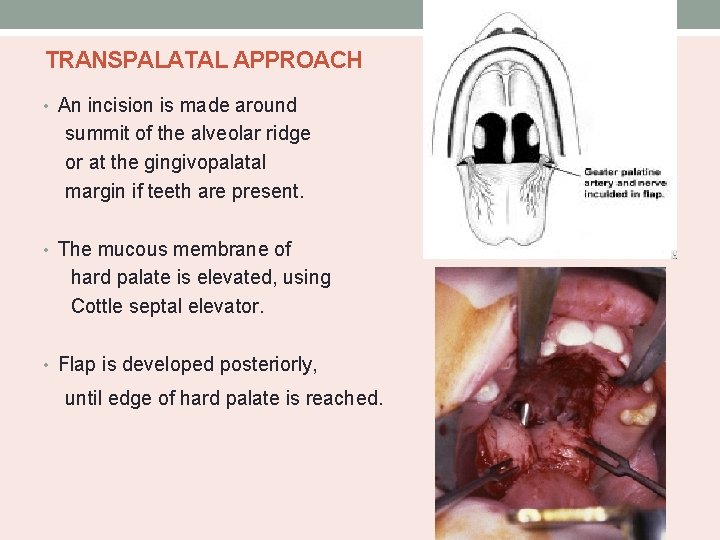

TRANSPALATAL APPROACH • An incision is made around summit of the alveolar ridge or at the gingivopalatal margin if teeth are present. • The mucous membrane of hard palate is elevated, using Cottle septal elevator. • Flap is developed posteriorly, until edge of hard palate is reached.